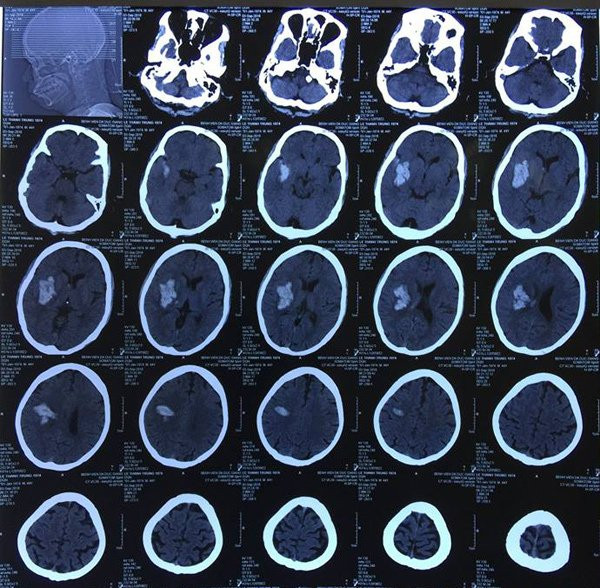

Bệnh nhân Lê T.T. (44 tuổi, Gia Lâm, Hà Nội) đến BV đa khoa Đức Giang khám do đột ngột đau đầu, nói ngọng. Bệnh nhân đã được các bác sĩ thăm khám, chụp CT sọ não, phát hiện trong não có khối máu tụ.

Tuy nhiên sau nhập viện, tình trạng bệnh nhân xấu đi rất nhanh, rơi vào trạng thái hôn mê kèm liệt nửa người trái. Kết quả chụp CT sọ não lần 2 cho thấy khối máu tụ trong não đã lan rộng, kích thước gấp 3-4 lần so với ban đầu, gây chèn ép các tổ chức xung quanh, sức khoẻ nguy kịch.

| Hình ảnh khối máu tụ trong não bệnh nhân |